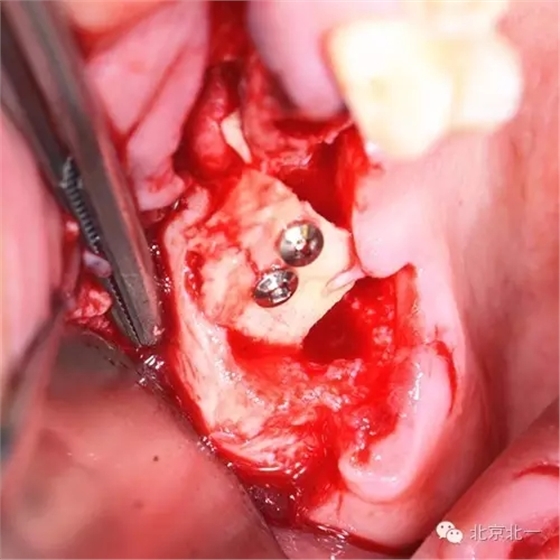

處置:拔除17,同期自體骨行ONLAY植骨。

圖四:取骨區(qū),下頜智齒位置,取骨工具用超聲骨刀。

圖七:骨塊堅強內固定